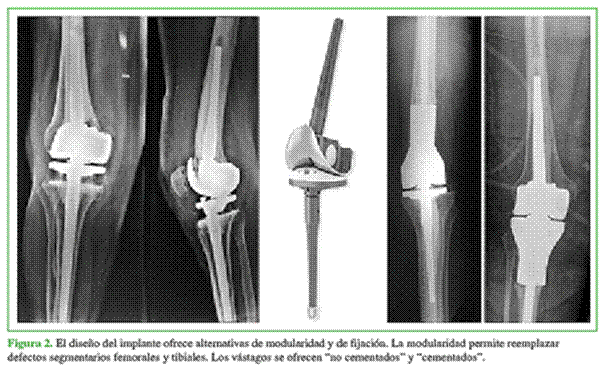

En el trabajo citado, el implante es ya presentado con el símbolo de “marca registrada” (“Endo-Modell®”) (“Scharnierendoprothese Endo-Modell®. Modell mit Zukunft”)5 (Figuras 1 y 2).

Precedentemente, en 1970, Buchholz y Engelbrecht diseñaron el prototipo St. George: prótesis de bisagra intracondílea con el principio de baja fricción; dicho prototipo original presentaba un eje bloqueado monocéntrico, respetaba la tróclea femoral y la fijación era cementada.

La cinemática más parecida a la rodilla natural, al proveer doble grado de libertad de movimiento.

La atenuación del estrés o la tensión en la interfase cemento-hueso.